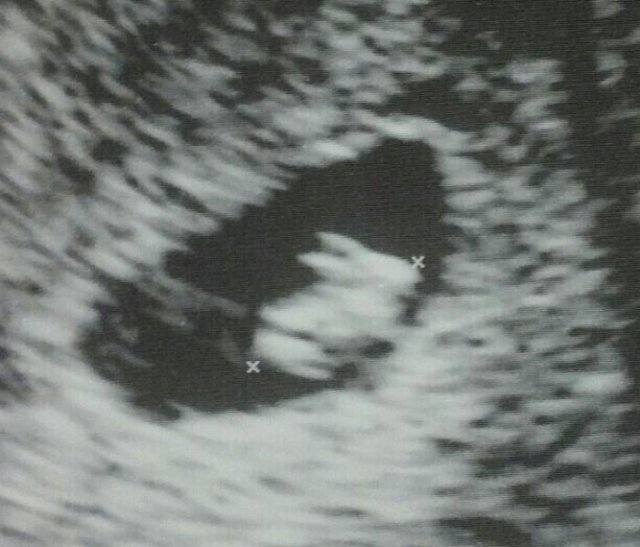

Congratulations! It’s a bunny!